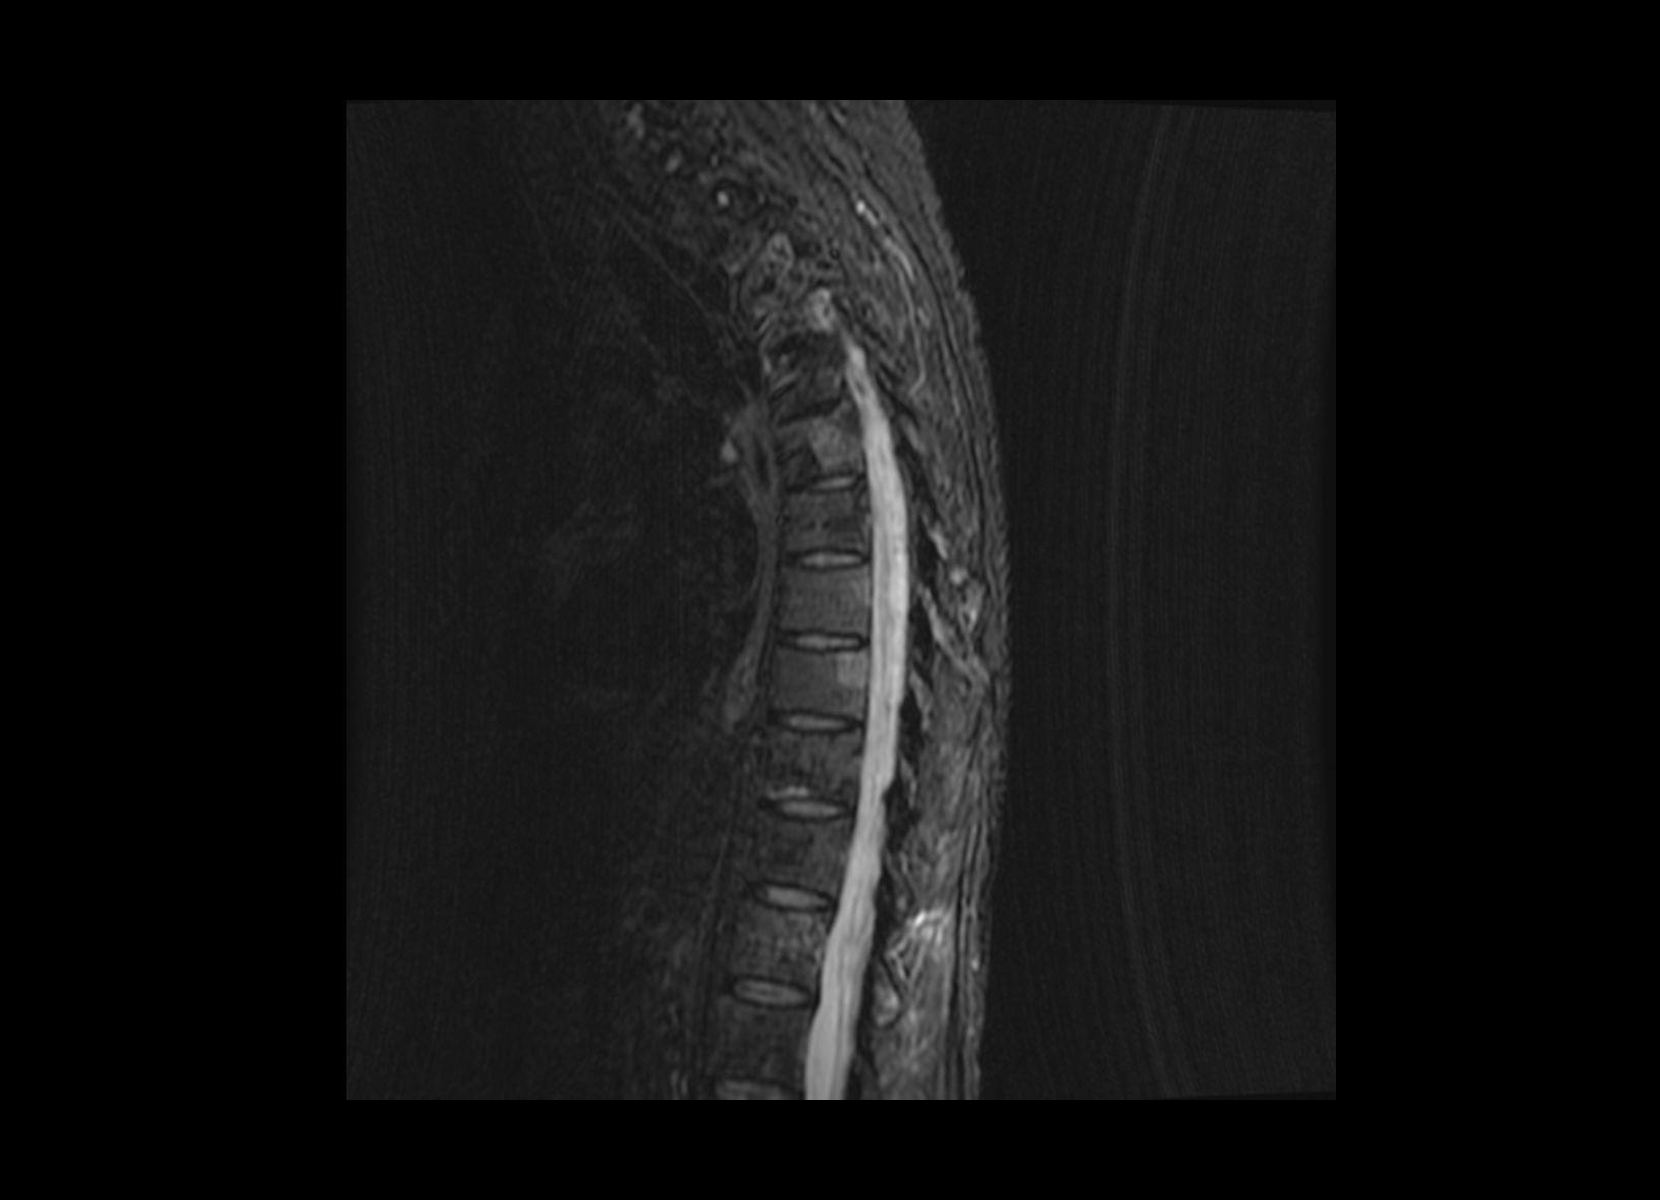

Conventional

STIR

SubtleSYNTH™

(Synthesized STIR)™

Trauma

GE 1.5T

C-spine